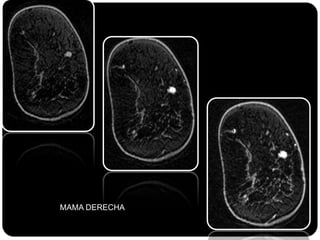

Paciente femenina de 66 años con historia clínica de 1er gesta antes de los 30 años y antecedentes de lactancia positiva, presenta una lesión palpable en la mama derecha. Los estudios radiológicos indican un diagnóstico de bi-rads 5, con biopsias revelando adenocarcinoma lobulillar infiltrante en la glándula mamaria derecha y adenocarcinoma ductal in situ en la izquierda. El caso fue evaluado por las doctoras Jacqueline Preciado Vargas y Beatriz E. González Ulloa.